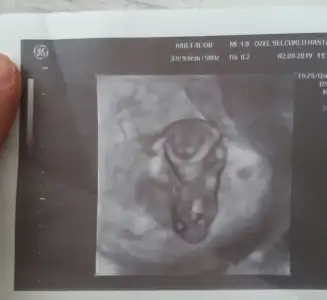

Tedavin hayırlı olsun canım. Rabbim güzel haberler almayı nasip etsin inşallah.❤❤❤Herkese günaydın. Dün muayene oldum. Dr. 7 gün kadar önce yumurtlamışsın dedi. Bunu nereden biliyorsunuz dedim. Yumurtanın şeklinden anlıyoruz dedi. Neyse hayırlısı ile başlayacağız tedaviye. Embriyoları genetiğe göndereceğiz. Sağlam çıkarsa transfer olacak.